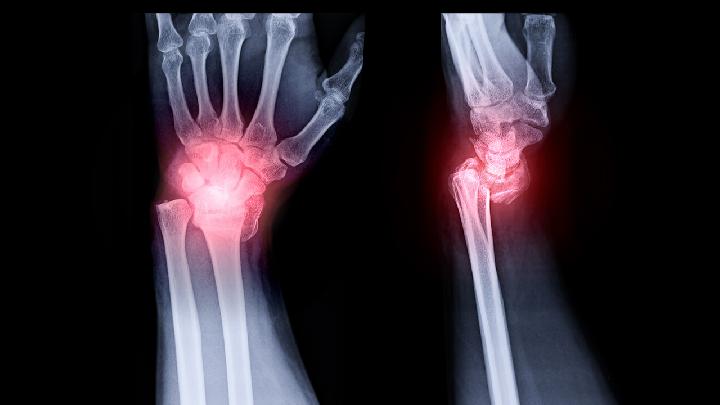

骨质增生是生活中普遍存在的一种疾病,可以说这些患者自患病以来一直受到该疾病的折磨。得了骨质增生是一件非常痛苦的事情,所以患者们都想要尽快的把病治好。那么,骨质增生医院治疗方法有哪些呢?